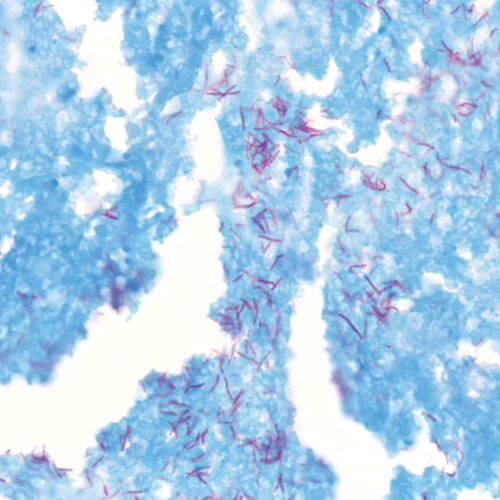

TB-Stain Histo kit

Three-reagent kit for staining acid-fast bacteria (pathogenic mycobacteria) in histology sections, sputum, smears and culture smears according to Ziehl-Neelsen. Heating of the carbol-fuchsin solution is avoided in this protocol hence omitting the release of hazardous phenolic vapors.